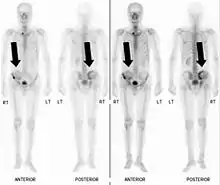

Bone scintigraphy

Also known as a bone scan, bone scintigraphy involves the injection of a small amount of radioactive tracer into the bloodstream. This tracer decays and emits radioactive energy which can be detected by a special camera. The camera produces a black and white image where areas shown as dark black indicate bone damage of some kind. If there is a black spot in the lumbar vertebrae (e.g. L5) this indicates damage and potentially spondylolysis. If this test is positive, a CT scan is usually ordered to confirm spondylolysis.[12]

Computed tomography

Commonly known as a CT Scan or CAT scan, this form of imaging is very similar to x-ray technology but produces many more images than an x-ray does. The multiple images produce cross-sectional views not possible with an x-ray. This allows a physician or radiologist to examine the images from many more angles than an x-ray allows. For this reason the CT scan is much more accurate in detecting spondylolysis than an x-ray. Bone scintigraphy combined with CT scan is considered the gold standard which means that it is best at detecting spondylolysis.[12][14]